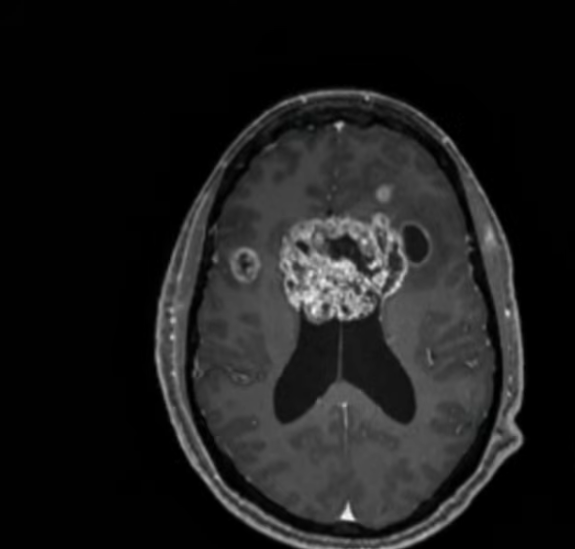

According to Jason, further tests confirmed a glioblastoma "multiforme," which he described as "a monster with tentacles spreading across the underside of my brain the width of a baseball."

Jason said doctors later told him that due to the tumor's placement — already in both hemispheres of his brain — it was considered a butterfly glioblastoma, making it impossible to resect fully.

An image of Jason Collins's cancer, from a video post dated December 11, 2025. | Source: YouTube/ESPN